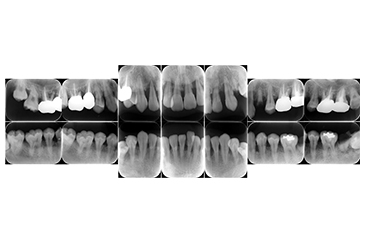

現在の治療費と異なる場合がございます。最新の治療費は料金表をご確認ください。CASE 1

基本情報

| 主訴 | 見た目をきれいにしたい |

| 治療期間 | 6ヶ月 |

| 治療費 | ジルコニアボンド(セラミックの被せもの)¥165,000×7(税込み) オフィスホワイトニング4回 ¥4,400×4(税込み) ホームホワイトニング¥11,000 |

| リスク・副作用 | かみ合わせがとても強い方の場合、稀に割れてしまうことがあります。 |

| 先生からの提案 | 上の前歯6本と右下の2番目の歯はセラミックの被せもので治療。 残りの下の前歯5本はプラスチックの材料で虫歯を治療し、 ホワイトニングをおこないました。白くなったご自身の歯の色に合わせてセラミックの 被せものを作成しています。 模型上で完成後をシュミレーションし、上の歯茎の位置をきれいに見えるように 揃えています。(外科処置はしていません) |